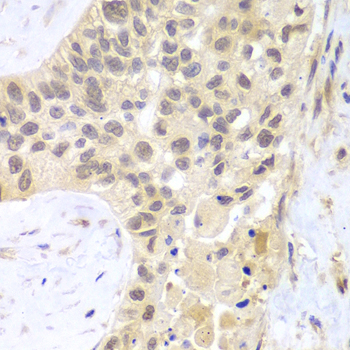

Immunohistochemistry - PSMC5 Polyclonal Antibody

Immunohistochemistry of paraffin-embedded human lung cancer using PSMC5 antibody at dilution of 1:100 (40x lens).